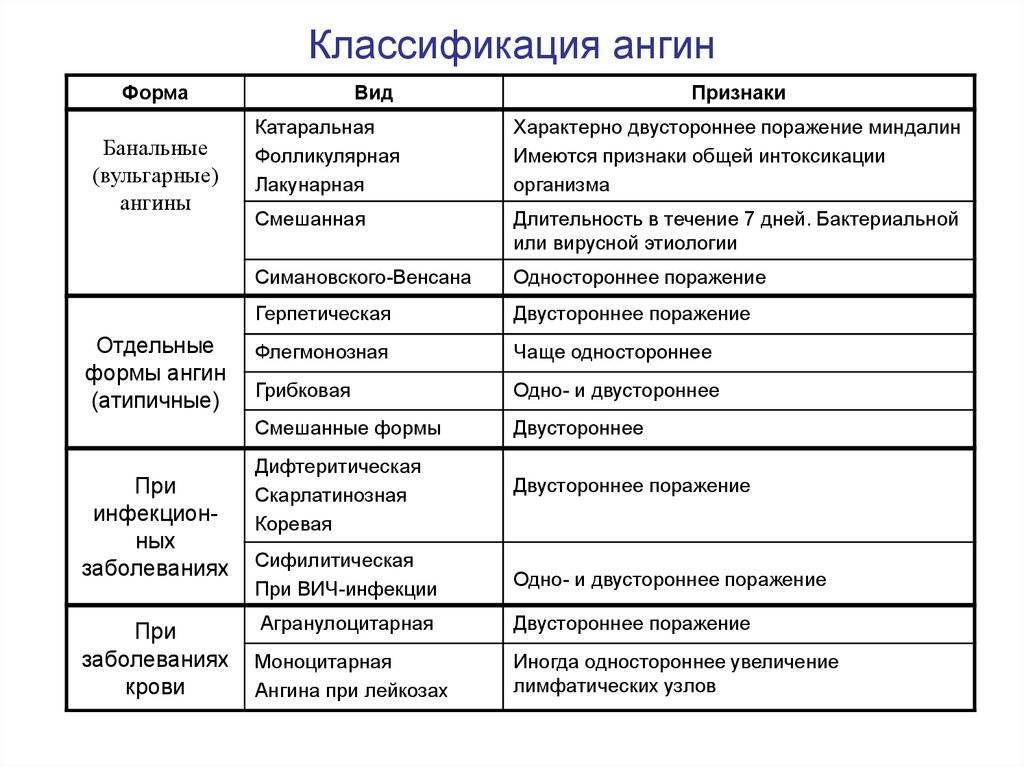

Классификация ангины

По степени воспаленности миндалин, ангина у детей может иметь несколько видов:

- катаральная. При осмотре зева видно, что небные дужки, миндалины увеличены и покрыты серозным белесоватым налетом;

- фолликулярная. Характерным признаком является наличие гнойных точек на миндалинах, размер которых может быть до трех миллиметров;

- лакунарная. Осмотр зева, открывает отекшие и сильно покрасневшие миндалины, покрытые налетом гноя, желтого цвета;

- фибринозная. Этот вид у детей встречается крайне редко. При осмотре видно, что миндалины покрыты пленчатым налетом, белесого оттенка гноя;

- гангренозная. На мягком небе и гортани видно плотный налет гноя серого цвета. Под гнойным налетом на миндалинах обнаруживаются язвы.